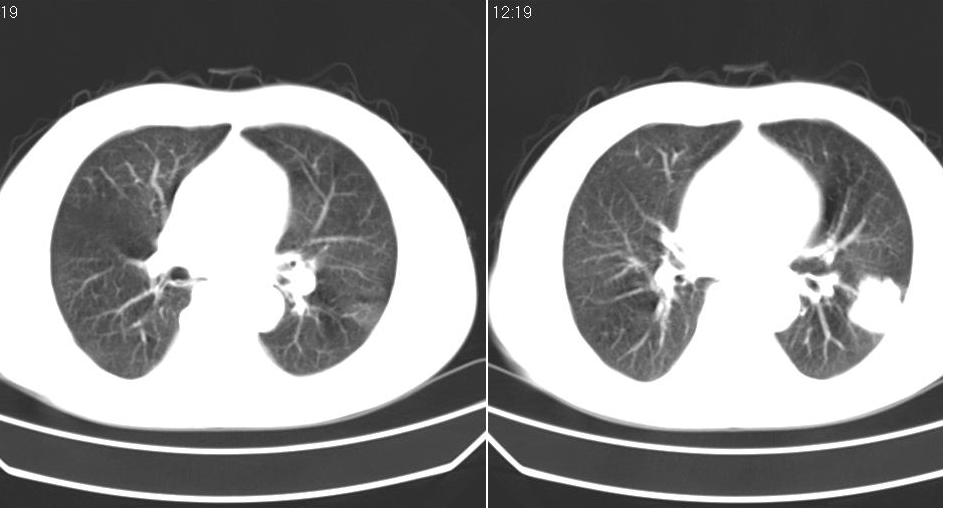

男 60岁,咳嗽,喀痰,胸闷,有吸烟史,正常图片未上传,请谅解。

考虑左肺下叶周围型肺癌可能性大。

左肺下叶周围型肺癌可能性大。